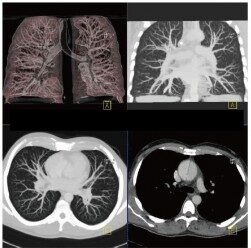

CT検査とはレントゲン(X線)を利用し身体の写真を撮影する検査です。

マルチスライスCT撮影装置

当院では、ドイツ・シーメンス社製マルチスライスCTを導入いたしました。

この装置は高速で回転し、短い時間で検査が可能な最先端マルチスライスCTで、従来の装置と比較して息を止める時間が短縮されます。また細かい情報を得ることができ、脳や腹部の血管や骨などの3D画像(立体再構成画像)を高精細に描出可能です。さらに、X線の被ばくも従来のCT装置に比べ低減されています。

頭だけではなく、全身のCTを撮ることが出来ます。